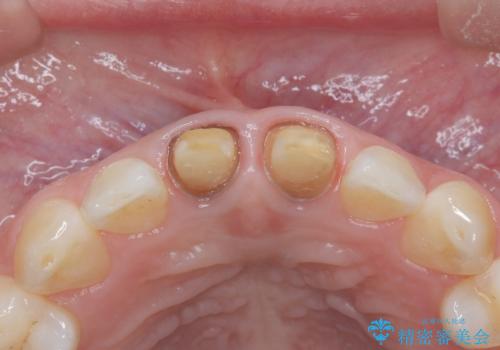

セラミッククラウンで前歯の変色を改善

- 前歯の変色が気になるというご相談をいただき、セラミッククラウンによる治療を行いました。

セラミッククラウンによって前歯の変色が改善され、また歯の形も希望の形態へ修正しました。